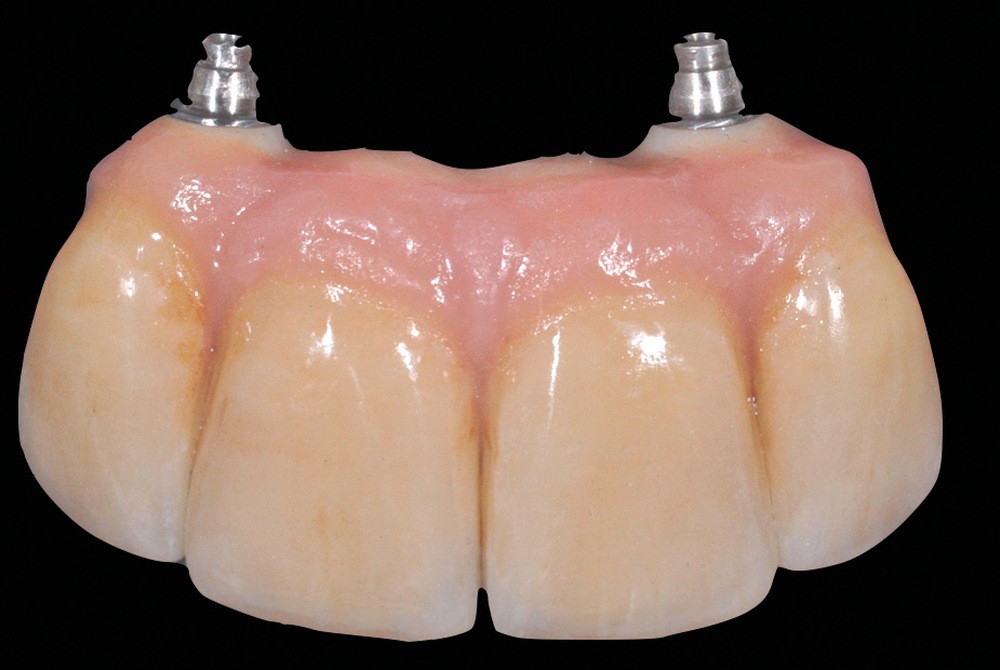

La seconde complication, plus grave, est le risque d’oublier des excès de ciment au niveau sous gingival. Ces derniers sont la cause principale avérée des péri-implantites et des pertes osseuses (fig. 2). Il est donc nécessaire de prendre toutes les précautions pour limiter au maximum ce risque.